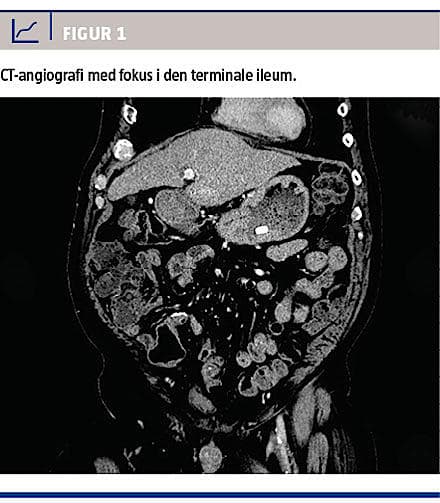

Ved indlæggelsen, der varede i 20 dage, blev patienten behandlet med daglige blodtransfusioner (28 portioner i alt) for at opretholde en hæmoglobinkoncentration på omkring 6 mmol/l. Der blev ordineret sædvanligt komaregime inkl. antibiotika, men han gik trods dette i coma hepaticum grad 4. Parakliniske undersøgelse ved indlæggelsen var upåfaldende med stort set normale lever- og koagulationstal fraset let påvirket P-albuminniveau, normalt P-natriumniveau og normal carbamid-kreatinin-ratio, hvilket ikke tydede på, at der skulle være en øvre blødning som årsag til patientens leverkoma. Der var ikke hæmatemese. På mistanke om en anden blødningskilde blev der foretaget CT-angiografi, hvor man initialt fandt normale forhold.

På mistanke om atrioventrikulær malformation supplerede man med en blødningsscintigrafi, som viste blødningsfokus i den terminale ileum. Retrospektivt kunne dette også ses på CT-angiografien (Figur 1). Da patienten var ude af sin koma og forventedes at kunne overleve kirurgi, fandt man ved laparotomi en venøs forbindelse fra en varicøs, umbilikal vene til den terminale ileum, hvor der var varicer. Man foretog tyndtarmsresektion af det afficerede område med anlæggelse af en primær anastomose. Det postoperative forløb var ukompliceret, og patienten gik på en længere orlov efter syv dage og havde fire måneder efter ikke været indlagt igen. Patologisvaret bekræftede, at der var tale om varicer i den terminale ileum.